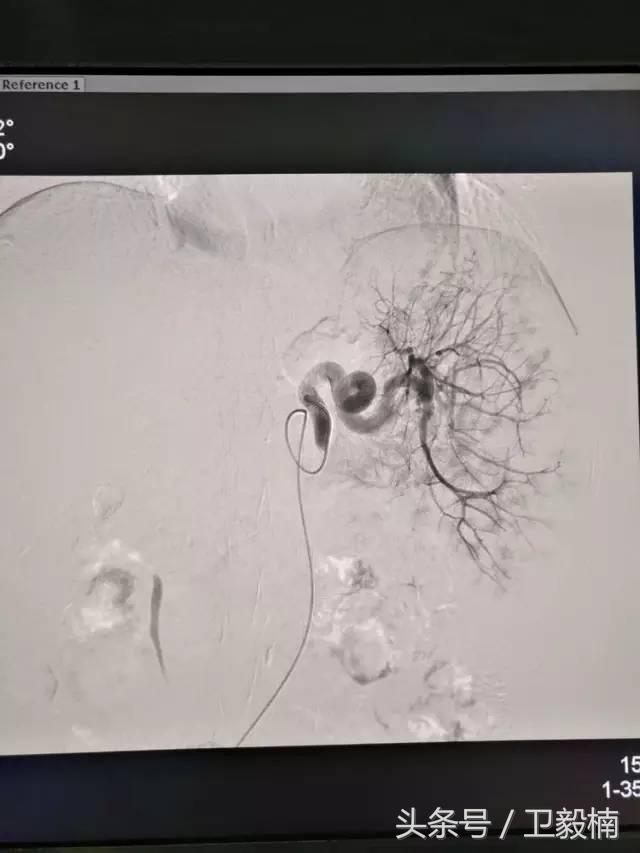

二、各类肿瘤的治疗:如肝癌、肺癌、食管癌、肾癌、胰腺癌、各种转移性肿瘤及妇科肿瘤、骨肿瘤等;

(2)肿瘤化疗 导管留置于供应肿瘤的动脉,滴注化疗药物,使局部用药浓度加大,避免或减轻化疗引起的全身反应。

2、经导管血管栓塞法(Transcatheter embolization)

经原血管造影的导管或特制的导管,将栓塞物送至靶血管内,一是治疗内出血如外伤性脏器出血、溃疡病、肿瘤或原因未明的脏器出血。另一是用栓塞法治疗肿瘤,因肿瘤循环部分或全部被栓塞物阻断,以达控制肿瘤之生长,或作为手术切除的一种治疗手段;亦可用于非手术脏器切除,例如注射栓塞物质于脾动脉分支内,即部分性脾栓塞,以治疗脾功亢进,同时不影响脾脏的免疫功能。

(1)选择性肿瘤供血动脉灌注化疗+栓塞治疗恶性肿瘤。